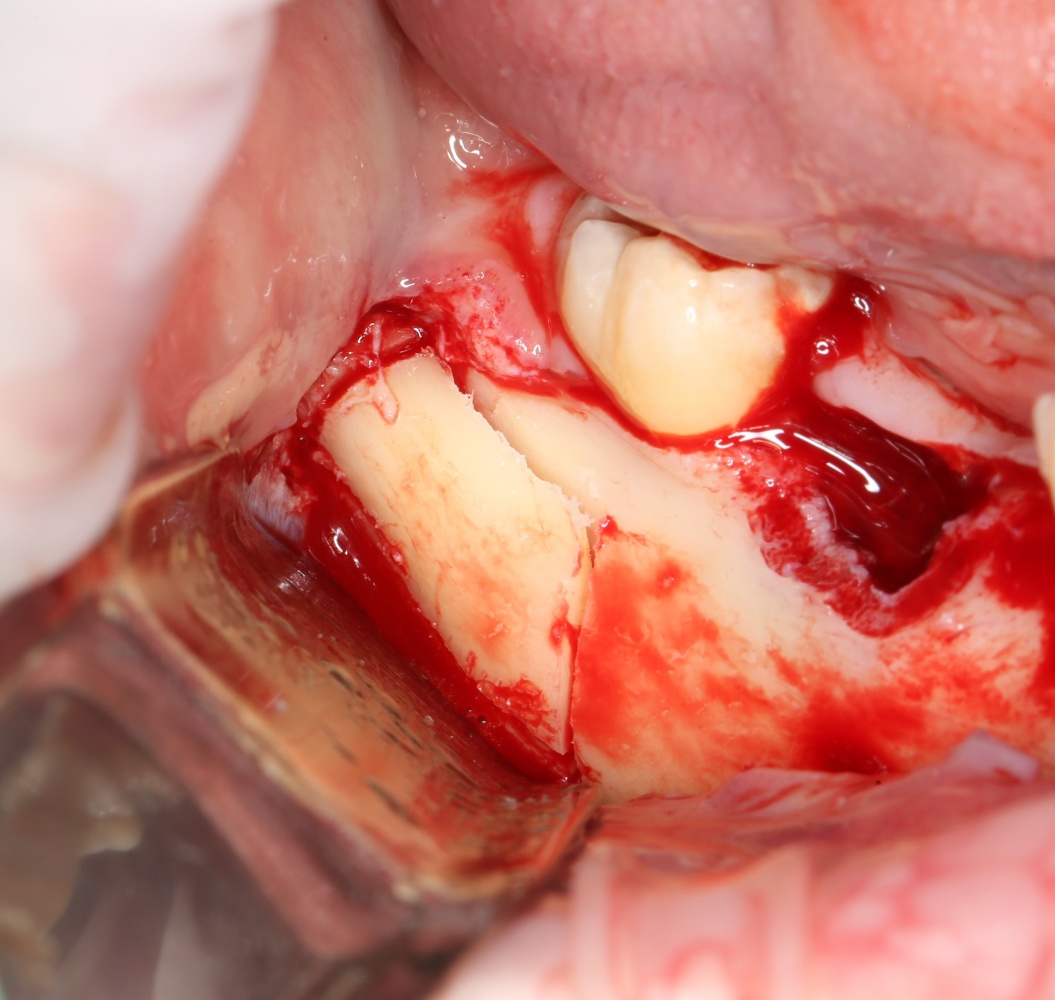

Забор костного фрагмента проводится с наружной косой линии с помощью ультразвукового пьезохирургического инструмента. Ничего сверхнового и супернеобычного тут нет, совершенно стандартная методика. С той лишь разницей, что молоток для этого используют только фашисты и только в гестапо использовать не нужно, всё делается усилием и ловкостью рук.

Нюансы начинаются с обработки принимающего ложа. Да-да, уважаемые друзья, одна из причин некроза блоков, их чрезмерной атрофии и прочих проблем — в отсутствии обработки принимающего ложа. Некоторые делают дырки, но правильнее и эффективнее поступить так:

то есть, просто снять слой кортикальной пластинки с участка, к которому будет фиксироваться костный блок. Почему? Читайте здесь>>.

Вторая особенность — мы не адаптируем и не обрабатываем костный блок invitro, а фиксируем его так, как есть:

после чего обрабатываем — доводим до окончательной формы альвеолярного гребня: